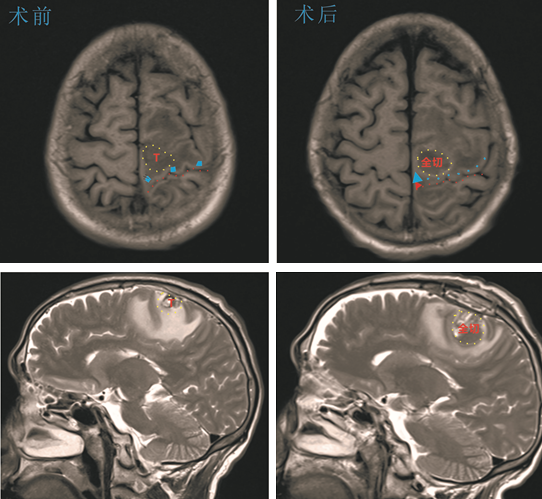

在杨孔宾教授的指导下,经过充分的术前准备,神经外科手术团队在显微镜下为陈大哥进行了功能区占位病变全切术,手术十分顺利,术后MRI复查提示肿瘤全切,病理提示胶质细胞瘤级别高,术后陈大哥的肢体功能得到保留,自主生活,顺利出院。在后期继续同步放化疗后,近期的复查也未见肿瘤复发。